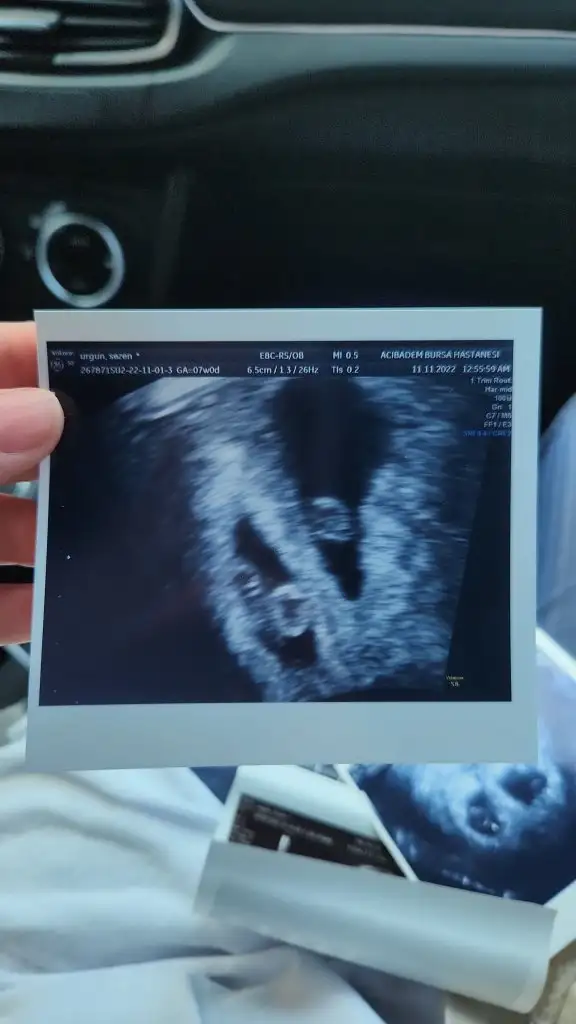

Kızlar merhabalar bugun kontrolüm vardı ve bebeğimin kalbi durmuşÇok kötü hissediyorum kendimi

Allah gayret ve sabır versin arkadaşımçok teşekkür ederim kızlar bilmiyorum inanın hiç bişey herşey yolundaydı geçen hafta keseyi görmeye gittiğimizde hatda kalp atışını görmüştük en son 110olarak duymuştukda,Bu hafta için yine çağırmıştı kalp atışı için dr Şok oldum gelişimi durmuş kalp atışı durmuş dediDünyam başıma yıkılmış durumda hissetiklerimi anlatmam imkansız.Kürtaj önermedi vajinal yoldan hap ile düşük yapıcam Sizleride çok fazla üzmek istemiyorum bebişlerinizi allah kucağınaza almayı nasip etsin iyi bakın onlara Benim için hakkımızda hayırlısı buymuş demek